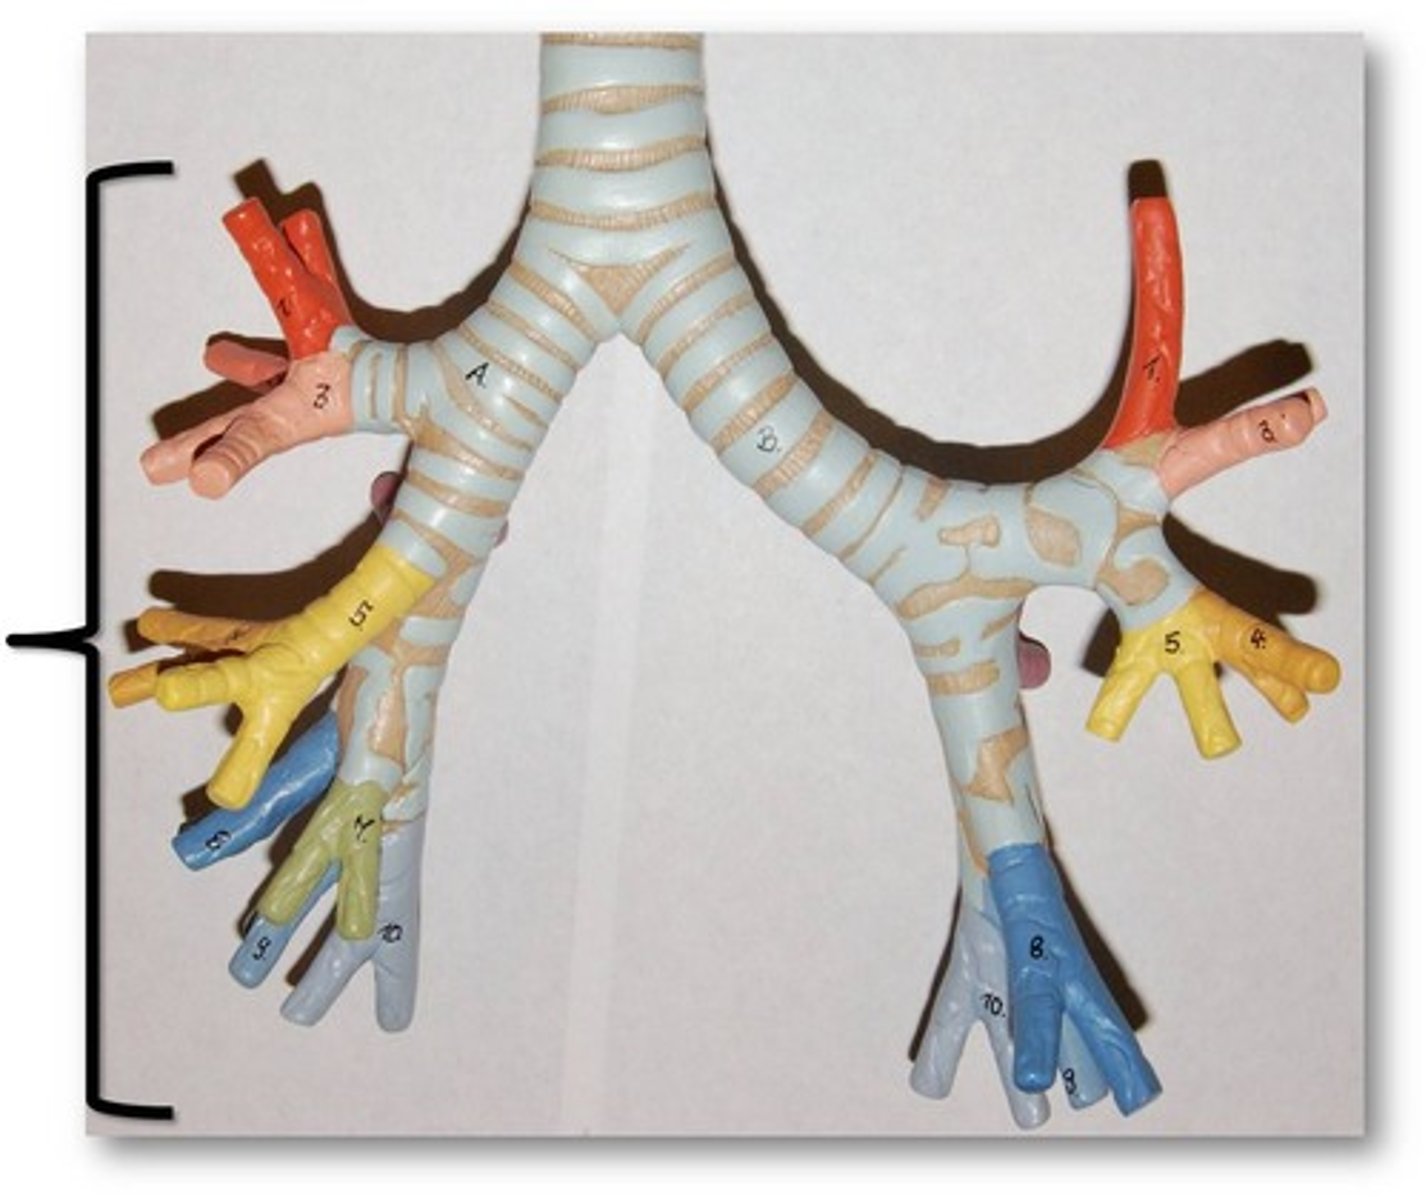

trachea

tube composed of cartilaginous rings and supporting tissue that connects the lung bronchi and the larynx; provides a route for air to enter and exit the lung

tracheal cartilage

C shaped rings of cartilage that give support to the trachea

bronchus

tube connected to the trachea that branches into many subsidiaries and provides a passageway for air to enter and leave the lungs

primary bronchus

The first branches of the trachea. There are two primary bronchi, one for each lung.

secondary (lobar) bronchus

The primary bronchi split into these smaller tubes within the lungs

tertiary (segmental) bronchus

branches of the secondary bronchi that divide into bronchioles; also called segmental bronchi

bronchial tree

collective name for the multiple branches of the bronchi and bronchioles of the respiratory system